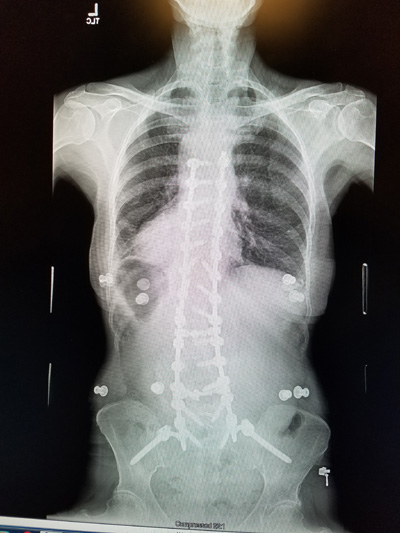

My year is up and I have had my 1 year x-rays and Surgeon appointment. Everything looks to be holding. I guess you would say that I no longer have scoliosis. I do still have that cardboard feeling in the muscles of my back. I mentioned to Dr. Kakarla that when I try to lift a gallon of milk the back goes into spasms and gets tighter. He decided that I needed another 30 sessions at physical therapy to make my upper body and legs stronger.

I still am doing the 4 mile hike. So with 3 times a week at PT and the hike my days are busy. Hope we can get started with our summer by Easter. Here are two views of my spine at my one year checkup.

The x-rays for the 5 year checkup show that everything is holding just fine. I was ready to have them make sure that the rods and screws were still doing okay. Remember those of us that have had this much surgery, find that doctors, family and people around us have a hard time remembering that we cannot do what others can. I carry my pictures of the x-rays in my phone.

Here are my January 2022 x-rays